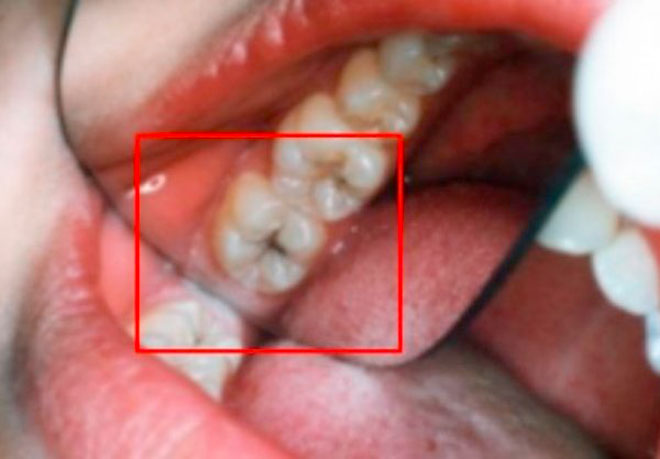

Poznato je da se karijes može izliječiti adekvatnom njegom i pravilnom ishranom.

Ima moćno svojstvo uklanjanja mrlja i fleka, stoga se koristi često i za pranje zuba. Takođe ima antibakterijski kapacitet koji eliminiše naslage i mikrobe koji prouzrokuju karijes i loš dah.